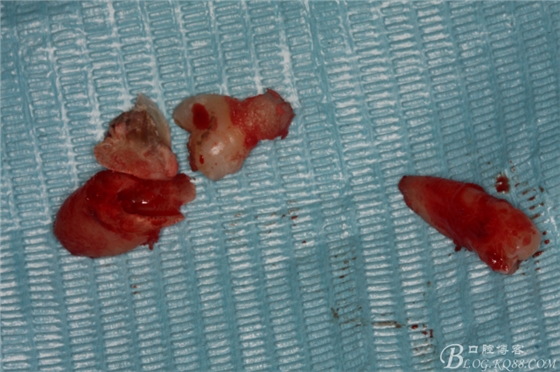

圖25.同樣的方法拔除37.

圖26.拔除34

圖27拔除的34、37、44、47.